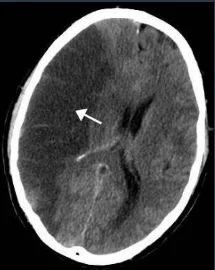

Ischemic strokes appear on non-contrast CT as {{c1::hypodense::description}} lesions and often don't become evident until > 24 hours

- vs. hemorrhagic strokes which appear hyperdense

- May be visualized between 6 - 24 hrs

Photo credit: Lucien Monfilsderivative work: Suraj, CC BY-SA 3.0, via Wikimedia Commons